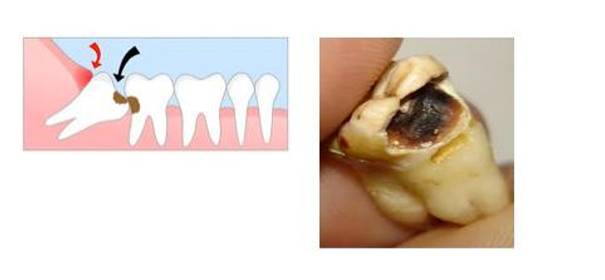

来看下面这张,从X光片上看,两颗智齿对颌萌出,位置看似也很正是吧。然而,拔下来之后是这样的:

已经烂掉了,有木有!

“智齿不痛、长得好像也还整齐,为什么医生还要建议拔掉?”

上图就是一个很典型的例子:看似好像长得还不错的两颗智齿,其实因为位置关系,不能很好的清洁、也缺乏正常的咬合关系,往往会有食物嵌塞、龋齿的发生,等到自己有症状的时候通常都很严重了。